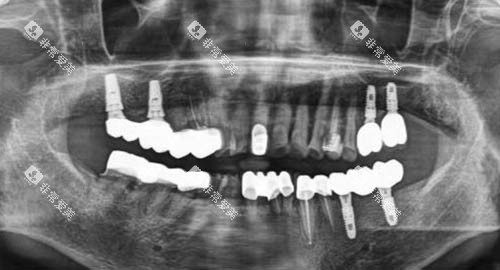

种植牙